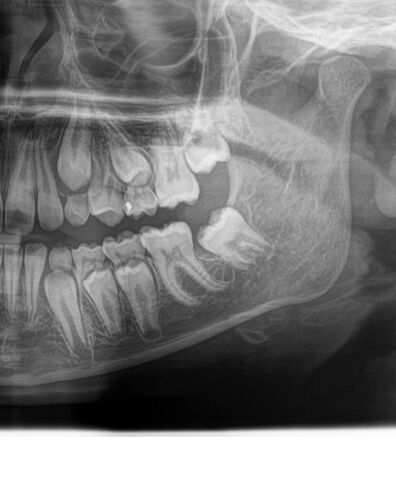

Такий знімок. Видно добре постійні, а молочні не хитаються.

Звичайно, я слухатиму лікаря! Але хочеться і досвід чужий послухати. 🤗 Чи це на знімку вважається, що зуб дуже близько і може вирости збоку?

У мого теж були такі зуби. Але у автора на знімку видно що нічого в бік не росте, корені молочних зубів розчинилися , постійні їх витісняють анатомічно правильно.

Ви бачите, що розчинились, так? Бо я не дуже розумію як вони б мали виглядати. Значить рвати буде не дуже боляче, надіюсь.

Нижние хорошо идут. А вот в верхнем ряду, средний зуб сам не выпадет, ничто его не выпихивает. Или он уже постоянный?

Він випав вже. Зверху лишився 3 і 5. Знизу 3,4,5 молочні

Зрозуміло. Знизу такого нема. Там значит важче буде